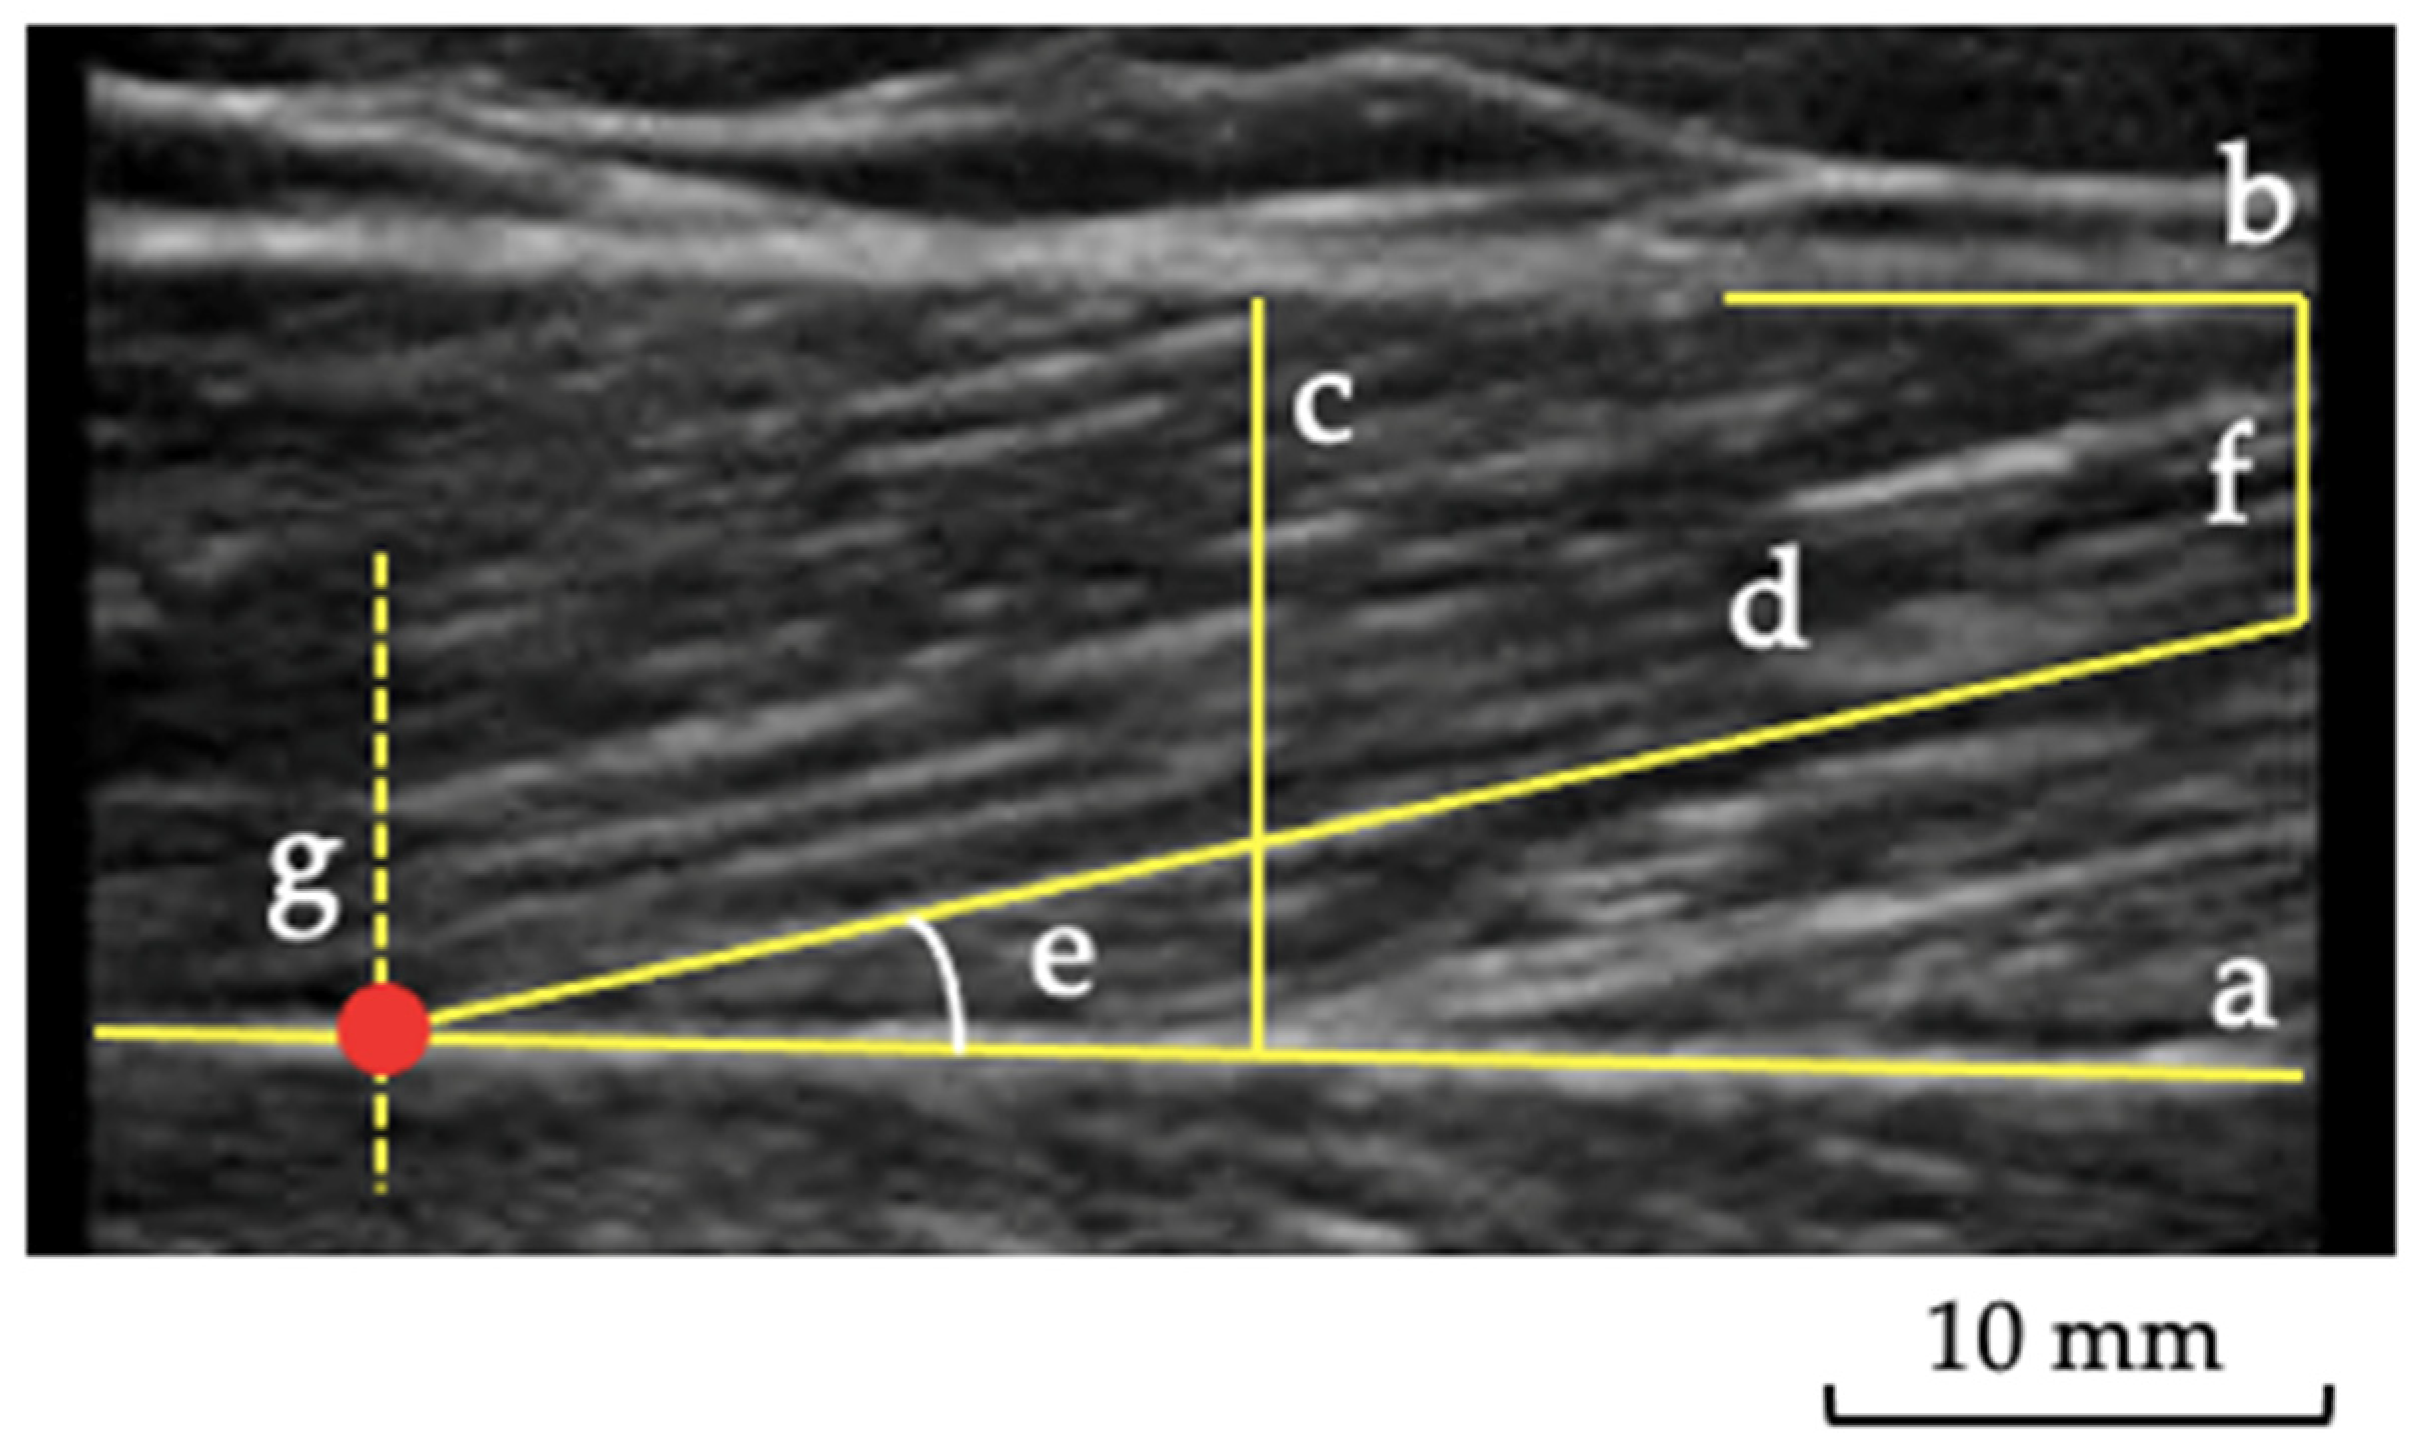

2.3. Muscle and Tendon Ultrasound Imaging